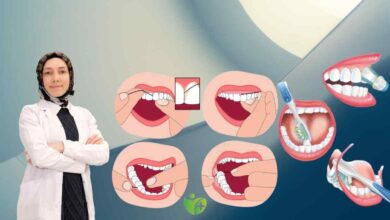

Diş Hekimi Yalçın Genç, ağızdaki en büyük tehlikenin 20 yaş dişleri olduğunu söyledi.

Diş Hekimi Yalçın Genç